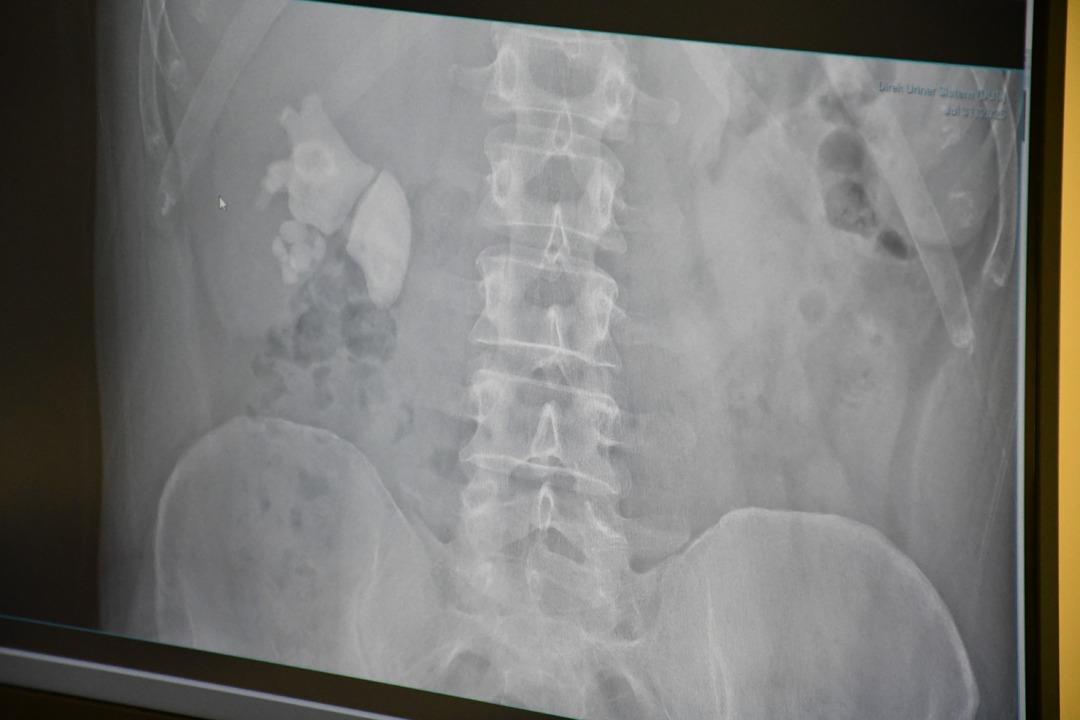

Kendilerini şiddetli böbrek ağrısı ile Yozgat şehrinin hastanesine uygulayan Evran’ın ayrıntılı sınavlarının ardından böbrekte yaklaşık 100 taş tespit edildi.

“Tamam böbrek taş doluydu”

Kamocanoglu, “Sağ böbrek muayenemiz taşlarla doluydu. Hasta hastayla tanıştı ve bu kadar büyük taşlarda büyük bir ameliyat olabilir ve hasta bazı deliklere girdi, ameliyatın sırtını gerçekleştirerek yapılması gerektiğini söyledi. Hasta kabul etti. Hasta ameliyatını Çarşamba günü yaptık.”